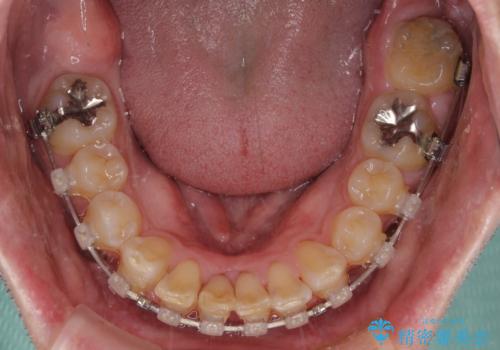

上顎歯列の叢生が著しかったため、上顎左右第一小臼歯2本を抜歯し、目立たないワイヤー装置にて治療を進めることとしました。

矯正治療後にはオーダーメイドタイプのオールセラミッククラウンを装着し、自然な口元に仕上がりました。